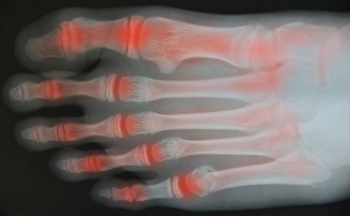

Arthritis is inflammation of one or more joints that causes pain, stiffness, and decreased mobility. It can result from joint injury, metabolic abnormalities, hereditary factors, or a misdirected immune system attacking healthy tissues. Symptoms often include swelling, tenderness, and difficulty moving the affected joints. Over time, arthritis can interfere with daily activities and overall quality of life. Chiropractic care focuses on improving joint function, reducing inflammation, and enhancing mobility through gentle adjustments and therapeutic techniques. By promoting proper alignment, chiropractors help ease pain and slow joint degeneration. If you are suffering from arthritis, it is suggested that you consult a chiropractor who can offer effective natural relief solutions.

Arthritis, a common condition affecting millions, causes inflammation, stiffness, and pain in the joints. It can make everyday activities challenging and significantly impact quality of life. While there is no cure for arthritis, chiropractic care offers a natural, non-invasive way to manage symptoms and improve joint function.

Chiropractors focus on enhancing joint mobility and reducing inflammation through gentle, targeted adjustments. By realigning the body and restoring proper movement, chiropractic care can help relieve the pressure on arthritic joints, alleviating pain and stiffness. Adjustments also support better circulation, which may help reduce inflammation around affected joints.

Chiropractic care can benefit both osteoarthritis and rheumatoid arthritis by focusing on reducing joint strain and promoting better movement.